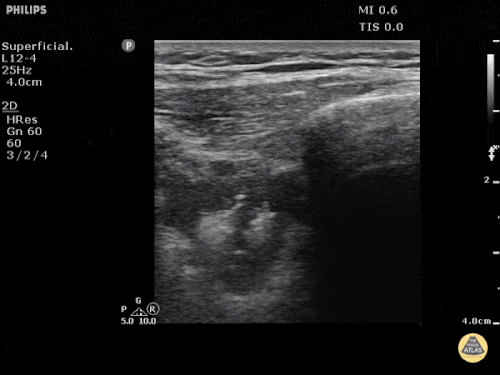

Question 2: You are called to evaluate a patient with COPD who presented to the ED with severe dyspnea. She is on BiPAP with severely elevated work of breathing. The ED is setting up materials to intubate her. The right anterior side of her chest shows this:

What is wrong with this picture? You slide the probe laterally around her chest. At the very posterior portion of her thorax, right next to her spine, you encounter this finding:

Questions:

- What is your differential diagnosis?

- What is your next step with regards to managing this patient?

- Is intubation a good idea, a bad idea, or a really really bad idea? Why?